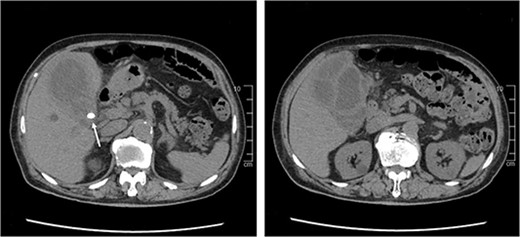

The results of the synovial fluid culture obtained by the previous doctor revealed K. pneumoniae on the next day, which is uncommon in PJI. Computed tomography (CT) imaging of the trunk was performed to screen for other sources of infection. CT revealed multilocular swelling of the gallbladder with diffuse wall thickening, gallstones lodged in the bile duct, and an abscess that had spread to the liver (Fig. 2). There was no bloating or pain in the right upper quadrant but Murphy’s sign was positive. We diagnosed cholecystitis with abscess that had been asymptomatic. We considered that emergency cholecystectomy would be high risk in view of his multiple comorbidities and the fact that he was on antiplatelet therapy. Instead, we elected to treat the cholecystitis first using antibiotics.

CT scan of the abdomen shows diffuse thickening of the gallbladder wall and gallstones lodged in the bile duct (white arrow).